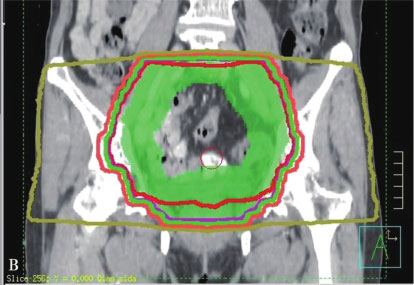

IMRT则是在3DCRT基础上的进一步发展,自1990年代早期IMRT被应用于临床以来,目前已成为一项常规开展的技术。IMRT通过多角度射野设置、多子野分割、滑窗等技术使均匀输出的通量分布变成不均匀分布,明显增加了靶区的剂量适形性,以避免或减少正常组织的照射,最大限度地限制治疗的副作用。IMRT的主要优势是其对凹凸靶区的适形能力,特别是凹面邻近重要器官时尤有优势。据估计,临床治疗的PTV有30%是凹形的靶区,因此可以从IMRT明显获益。另一方面,IMRT治疗方案是在治疗计划系统内通过逆向治疗计划的设计而得到,可以获得较正向计划方法更优的靶区适形性和更窄的侧向半影。通过调节每个射野的通量强度,在肿瘤靶区和正常器官之间形成一个很窄的剂量梯度,通常允许至少95%的PTV接受规定的处方剂量,同时保证周围正常组织的受量在既定的耐受范围之内。图7-2-1为IMRT与3DCRT技术的剂量分布图,其中图A、B、C所示为3DCRT剂量分布,图D、E、F所示为IMRT剂量分布,其中IMRT的剂量靶区适形性明显优于3D-CRT。

图7-2-1 IMRT与3DCRT技术的剂量分布图

A~C.为3DCRT剂量分布;D~F.为IMRT剂量分布